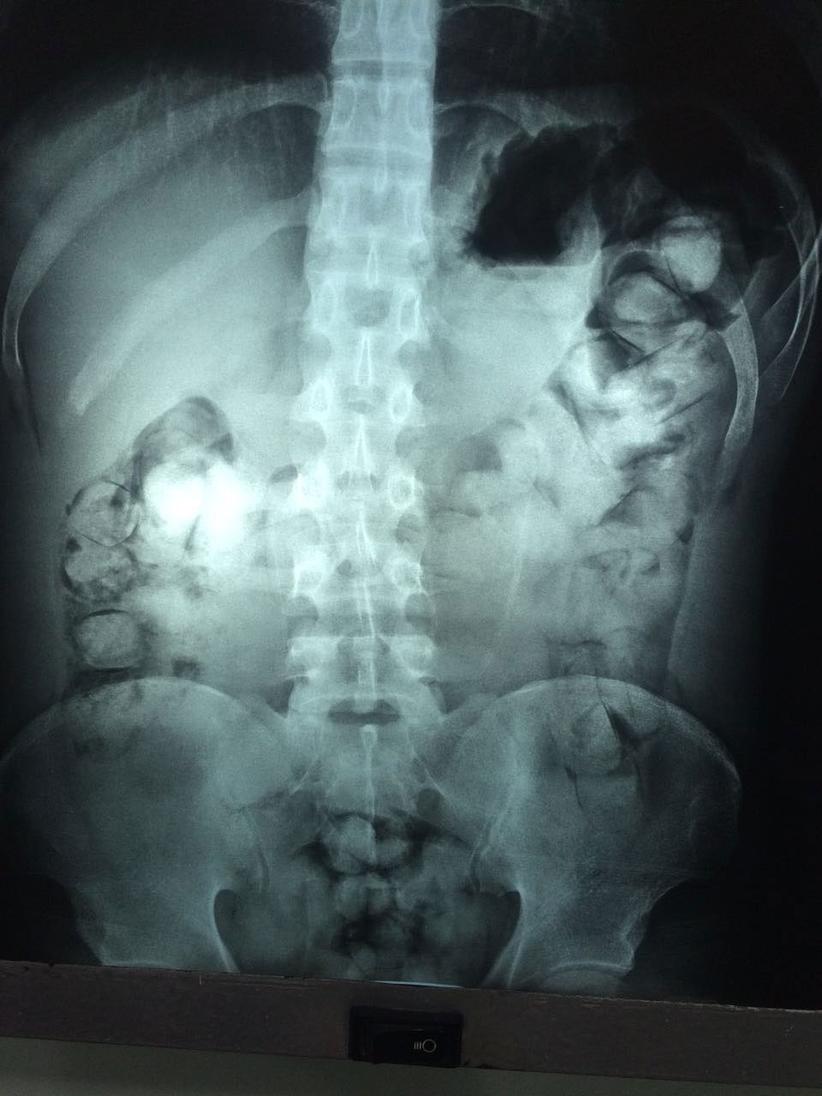

De acordo com informações de policiais da equipe da Estratégia de Fronteira (Esfron), com o jovem foi apreendido 100 cápsulas de cocaína. 25 estavam nos bolsos da calça e amarradas no calcanhar.

O restante do entorpecente foi localizado dentro do estômago do suspeito. Ele foi encaminhado ao hospital do município, onde foi internado para remoção da droga.